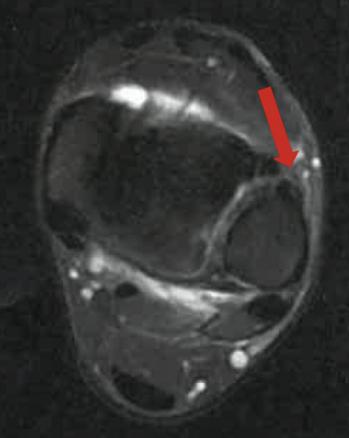

À J15, une gêne fonctionnelle importante liée à la douleur à l’appui et une sensation d’instabilité persistent. L’inspection ne met pas en évidence d’hématome mais un discret épanchement tibio-talien. La mise en compression de la syndesmose (« test de Hopkinson » ou squeeze test ; fig. 1) déclenche une franche douleur remontant le long de la face antérieure du tiers inférieur de la jambe. Il n’existe, en revanche, pas de douleur à la palpation de l’insertion talienne du ligament tibiofibulaire antérieur (LTFA).